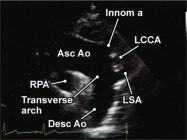

| 2.27. Mặt cắt trên hõm ức ghi hình quai động mạch chủ (video 68 |

||||||||

|

|

|

Cửa sổ siêu âm trên hõm ức

Từ vị trí 12 giờ xoay dần đầu dò hướng về vai trái (vị trí 1 giờ) và nghiêng đầu dò để chùm siêu âm cắt qua núm vú phải và đỉnh xương bả vai trái. |

Động mạch chủ lên (Asc Ao)

Quai động mạch chủ (tranverse arch) Động mạch chủ xuống (Desc Ao) Động mạch vô danh (Innom a) Động mạch cảnh gốc trái (LCCA) Động mạch dưới đòn trái (LSA) |

|||||